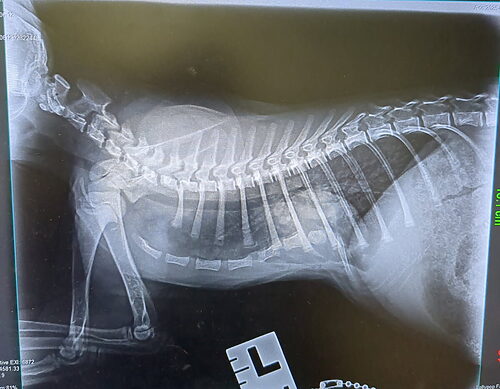

Vanilla Bean was born with a rare congenital condition called pectus excavatum, in which the sternum curves inward toward the chest cavity. For a growing kitten, this deformity can place dangerous pressure on the heart and lungs, causing serious health problems if left untreated.

During his intake exam, our veterinary team immediately recognized the sunken shape of his chest. At just nine weeks old and weighing only three pounds, Vanilla Bean needed surgery if he was going to have a healthy future.

When the day of the operation arrived, Dr. Young was nervous but determined. Vanilla Bean’s case was severe, one of the worst her professor had ever seen. The surgery presented risks, but the prospect of giving Vanilla Bean a significantly improved quality of life was all the motivation Dr. Young needed. The two veterinarians got to work, painstakingly threading each suture under the sternum, careful not to damage any internal structures, especially the heart. After completing all twelve sutures and anchoring them to an external splint, the surgery was complete.